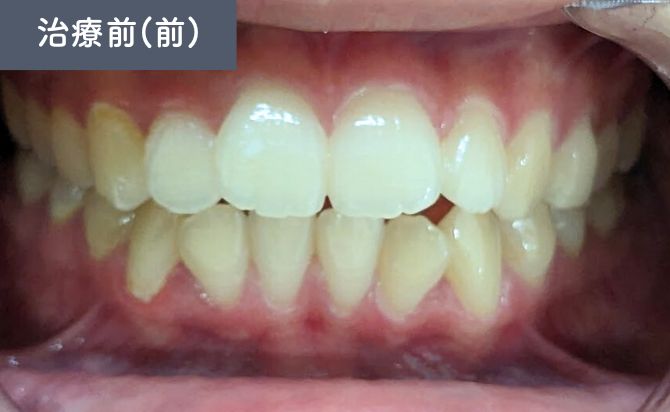

歯並びの変化(正面)

Before